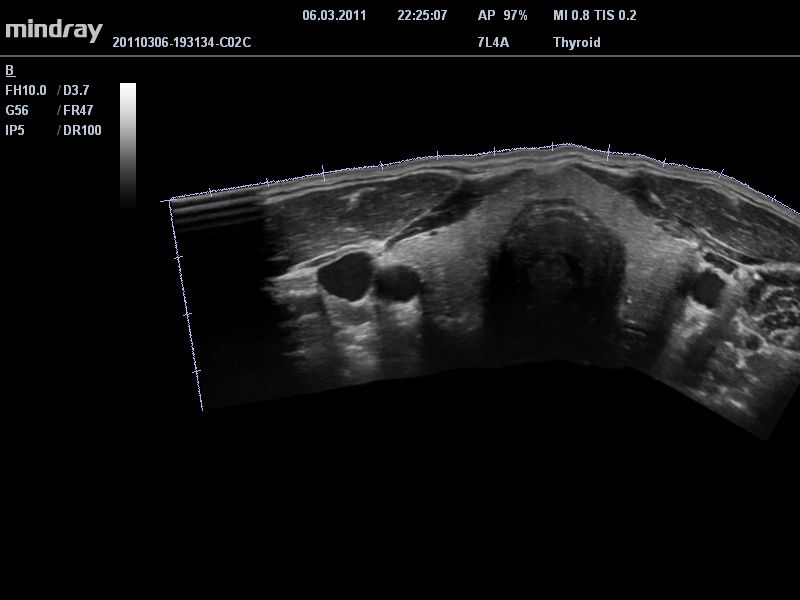

• Линейный ультразвуковой датчик Mindray 7L4A

• Режимы сканирования: B/M/CFM/PDI/Направленный PDI/PW, HPRF, Тканевая гармоника, М- и цветной М-режим.

• iClear™: технология подавления зернистости увеличивает контрастное разрешение поврежденных участков без ущерба для пространственного разрешения.

• iBeam™: позволяет более точно определять границы благодаря объединению нескольких изображений, полученных под разными углами, в одно изображение в режиме реального времени.